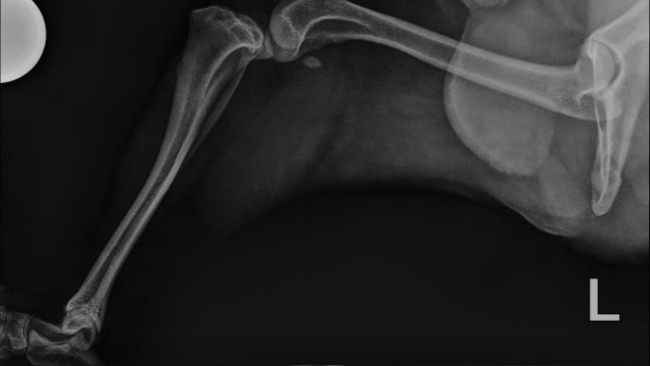

Gomez ma już za sobą dwie poważne operacje — dzielnie zniósł wszystko, mimo trudnych chwil i wielu ograniczeń. Każdy dzień to walka o jego sprawność, komfort i powrót do normalności.